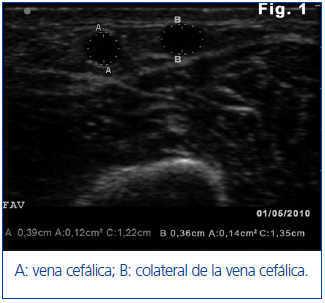

Ante estos hallazgos se realiza ecografía del acceso vascular (AV) portátil (EcoAVP) en la sala de HD (figura 1) y se observa ausencia de estenosis en la unión arteriovenosa, doble sistema venoso con colateral que nace a 3 cm de la anastomosis arterial y grosor equiparable de las dos venas (diámetro: 0,39 vs. 0,36 cm, área: 0,12 vs. 0,14 cm2). Se detectan dos estenosis en la porción proximal de la vena cefálica.

Figura 1. Primera ecografía en modo B del acceso vascular donde se observan dos venas de calibre equiparable